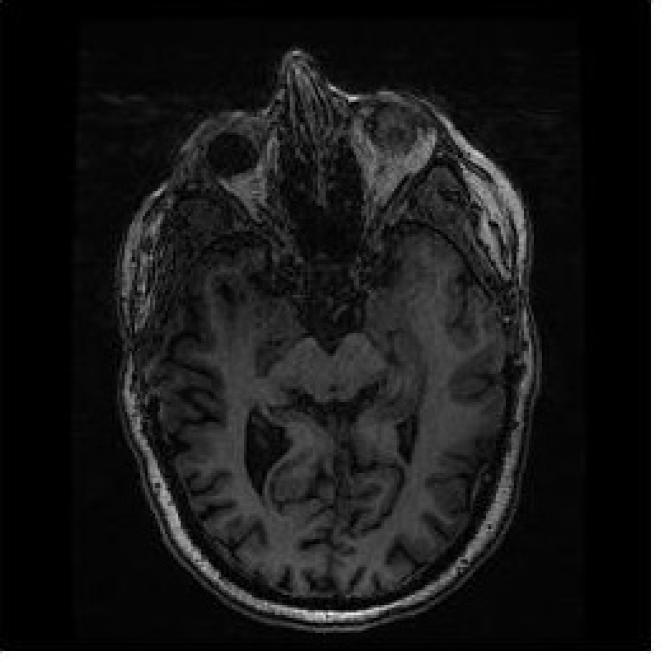

Fig.9 shows a comparison of reconstructed medical images at different signal-to-noise ratios (SNR) of 5 dB, 10 dB, and 20 dB. The results demonstrate that as the SNR increases, the quality of the reconstructed images also improves. Additionally, Fig.10 illustrates the relationship between signal-to-noise ratio (SNR) and bit error rate (BER) which is a key indicator of the performance of an OFDM system in image transmission. The figure shows that as SNR increases, the BER decreases, indicating that the OFDM system performs better in terms of image transmission quality. It also highlights the importance of having a high SNR in achieving reliable image transmission using the OFDM technique. In comparison to previous work on secure image transmission, our proposed method has demonstrated superior performance in terms of bit error rate (BER). Specifically, our method achieved a lower BER of 0.005 compared to 0.007 in SNR=30db obtained in [8]. This highlights the effectiveness of our proposed approach in improving the security and reliability of image transmission.

(a) (b)

(c)